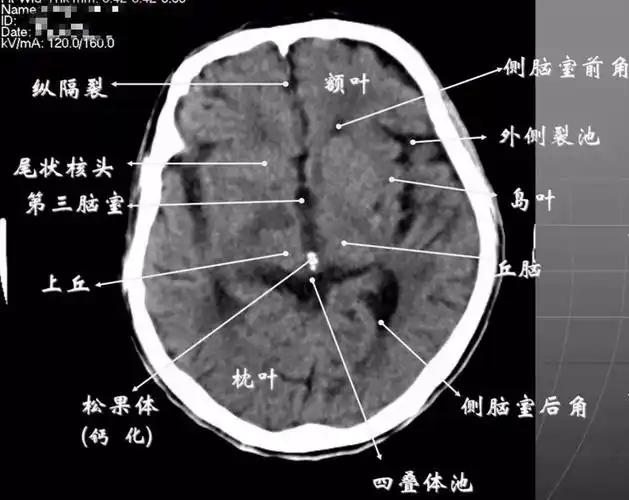

颅脑ct影像断层解剖ppt

颅脑ct怎么看?正常和异常影像分别是什么?干货满满!